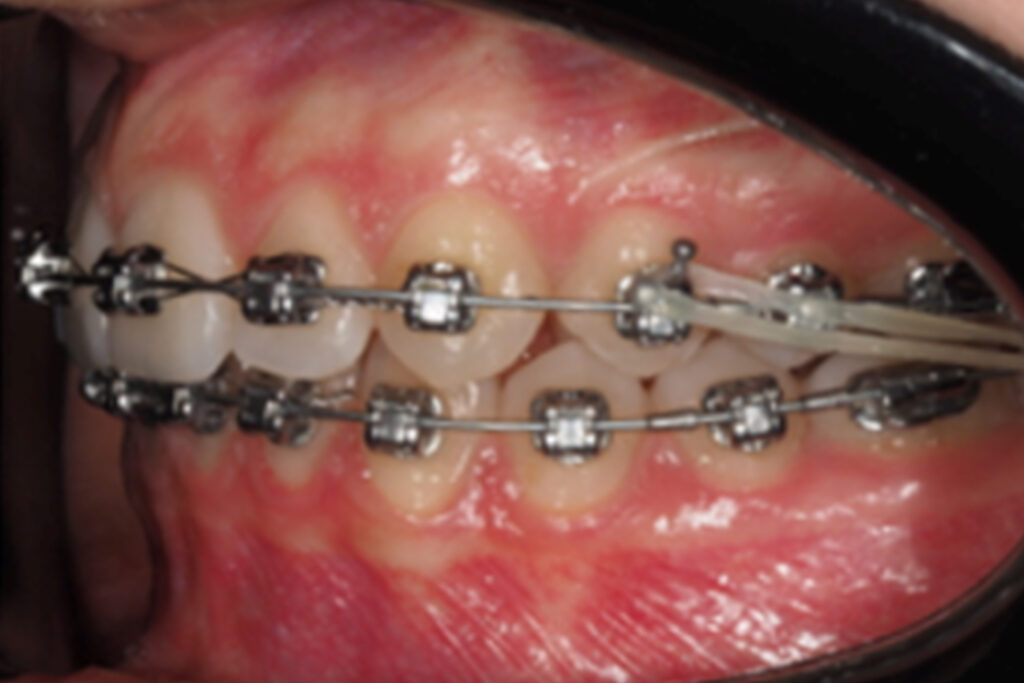

While 6 weeks with 18×275 CuNiTi upper and lower archwire, a panoramic reposition visit wasplanned, and LL1 was replaced for second-order correction. The LL8 was extracted at this momentdue to patient´s discomfort as the others were planned to be extracted after bracket debonding.

March 2023

May 2023